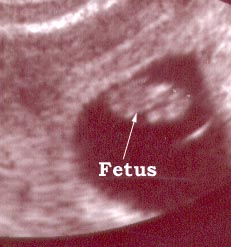

Here are a few sonar photos to illustrate the appearance of the fetus at different stages of a pregnancy.

Photo One

This a six week pregnancy and a transvaginal probe was used.